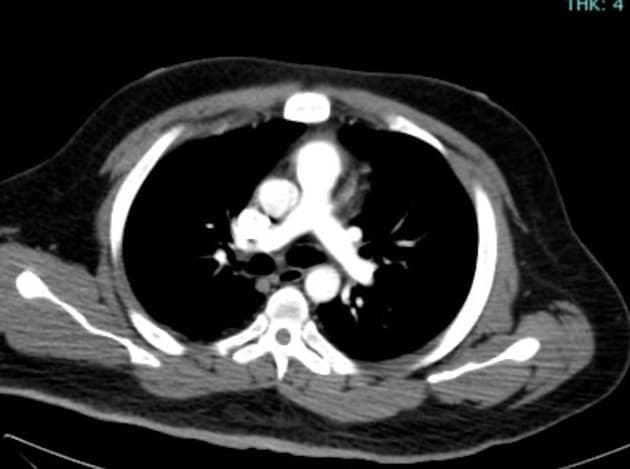

- Các nhánh đường mật trong gan (intrahepatic biliary radicles) giãn nhẹ.

- Ống mật chủ (common bile duct) giãn, thấy nhiều viên sỏi nhỏ có tín hiệu thấp ở đoạn cuối.

- Túi mật (gallbladder) căng giãn, chứa nhiều viên sỏi nhỏ.

- Tụy (pancreas) to lan tỏa và phù nề, xung quanh có dịch quanh tụy lan dọc theo các khe mỡ vùng sau phúc mạc, rõ hơn ở phía bên trái.

- Ống tụy (pancreatic duct) có vị trí, chiều dài và đường kính bình thường, cấu trúc bên trong đồng nhất, bờ trơn đều.

Sỏi túi mật (cholelithiasis) và sỏi ống mật chủ (choledocholithiasis) là những nguyên nhân phổ biến gây viêm tụy cấp (acute pancreatitis). Trong trường hợp này, viêm tụy cấp được phát hiện trên hình ảnh cộng hưởng từ đường mật tụy (MRCP) được thực hiện do có triệu chứng vàng da tắc mật và đau vùng thượng vị.

Viêm tụy cấp là một tình trạng lâm sàng phổ biến, thường do sỏi mật gây ra, đặc biệt khi chúng làm tắc ống mật chủ tại nhú tá lớn (ampulla of Vater). Trường hợp này cho thấy các hình ảnh điển hình trên MRCP bao gồm to toàn bộ tụy, dịch quanh tụy và dấu hiệu tắc nghẽn đường mật do sỏi ống mật chủ. Sự hiện diện của nhiều viên sỏi nhỏ ở đoạn cuối ống mật chủ xác nhận nguyên nhân bệnh. Chẩn đoán sớm bằng MRCP cho phép xử trí kịp thời, bao gồm nội soi mật tụy ngược dòng (ERCP) để lấy sỏi. Việc phân biệt viêm tụy cấp với các nguyên nhân khác gây đau bụng và vàng da như viêm đường mật hay ung thư tụy là rất quan trọng vì các bệnh này đòi hỏi can thiệp khác nhau.